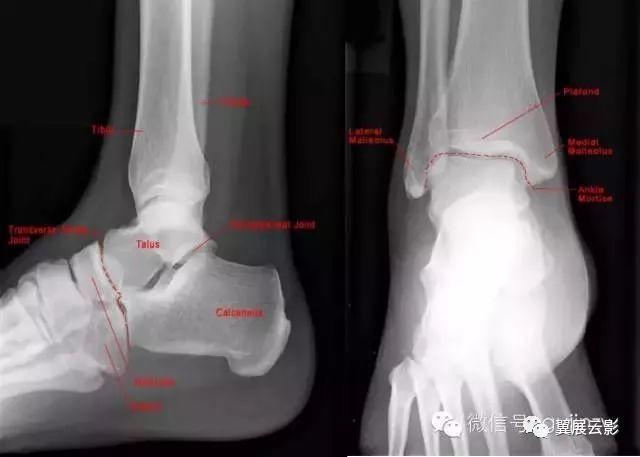

42张x线片带你读懂不同部位骨折

脚踝骨折